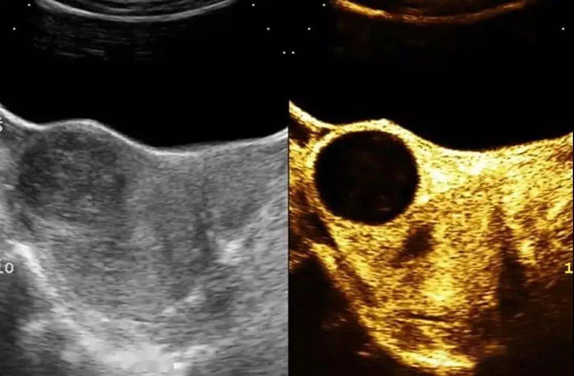

子宫肌瘤超声造影表现为增强早期周围假包膜环状增强,内部增强与肌层同步,达峰后,肌瘤呈均匀或不均匀稍高增强,增强晚期瘤体与肌层造影剂开始消退,周围假包膜消退时间较长,与肌层出现明显分界。

子宫腺肌瘤由于没有假包膜,增强早期呈点状或短线状增强,与周围肌层同步,呈稍高增强或等增强,增强晚期与肌层同步消退或稍早于肌层消退,与其周围无明显边界。当热消融和栓塞有效时,显示病灶区无造影剂灌注,复查发现病灶区无造影剂灌注,病灶逐渐缩小。

聚焦超声消融子宫肌瘤